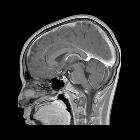

MRI

MRI is the modality of choice for confirming the diagnosis, although it is often unnecessary. It will demonstrate the sella to be filled with CSF and the infundibulum can be seen to traverse the space, thereby excluding a cystic mass. This is known as the infundibulum sign .

Trying to assess the significance of an incidentally identified empty sella can be difficult, especially if no pertinent clinical notes are available. The likelihood of it representing undiagnosed intracranial hypertension correlates with the patient's age and gender (middle age and female), orbital findings (flattened globes and optic nerve sheath prominence) and subcutaneous fat thickness as a marker of weight, although no cut-off measurements are available .